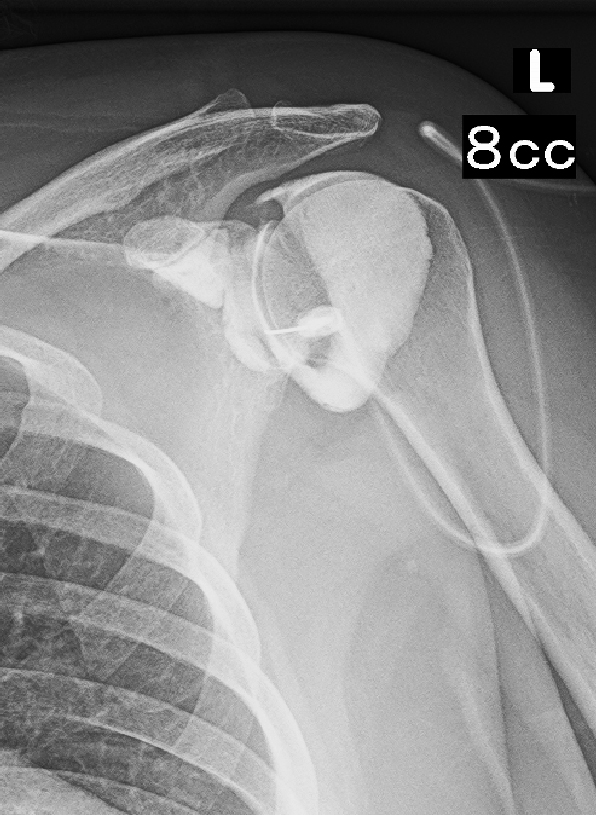

肩の状態を評価するために、治療を兼ねて肩関節造影という検査を行ないます。

左肩関節の大きさ(容量)は8㎖で、肩の関節包という運動領域を規定する構造は半年の期間で大きく縮小していることが把握されました。通常の成人の肩関節包の容量は20㎖前後であるからです。